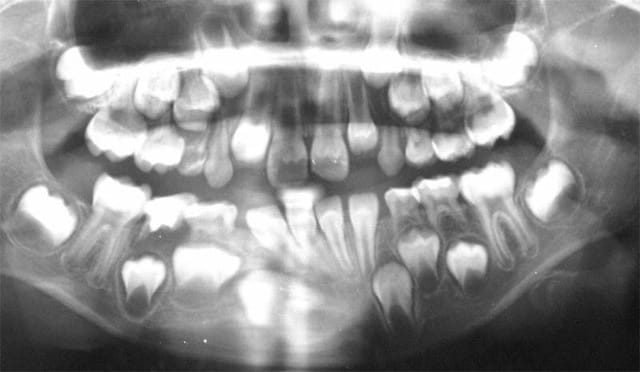

Cette Rx. n’est pas normale. Il y a qq. chose qui cloche.

Qq. chose que la nature ne sait pas faire.

Ces incisives Inf. en cors de chasse c’est pas normal !

J’ai demandé une autre Pano. Le pitchoun a dérapé sur la cale Rx. Interincisive.

Cette pano appelle deux critiques :

La première est liée aux paramètres physiques du cliché. On ne voit aucun détail sur les couronnes des dents qui paraissent laiteuses, de même que certaines parties osseuses sont excessivement blanches.

Ceci vient d’un mauvais réglage du générateur.

On sait qu’une image trop blanche ou trop noire provient des mA (quantité d’électrons émis) et que le contraste est donné par les kV (puissance pour traverser les tissus).

Je suggérais donc dans un premier temps de diminuer les mA, puis d’essayer de diminuer les kV.

La seconde est liée à la position du sujet. Une image agrandie des dents signe une position trop en arrière du patient, une image rétrécie signe une position trop en avant. Comme les dents ont ici une différence de taille importante dans un secteur intermédiaire, la probabilité d’un déplacement du sujet pendant la rotation du générateur est importante.

Cela dit, il n’y a aucune certitude quand à la position de 43 qui pourrait tout à fait être dans une position ectopique.

Cette radio n’a donc aucune valeur et on ne peut ici faire aucun diagnostic.

Daniel